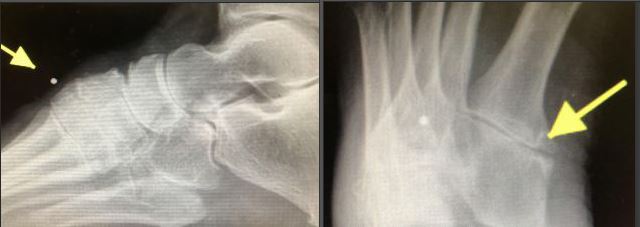

Query: Lateral Column Fusions vs. Arthroplasties of the Metatarsal Cuboid Joints

I have an active slightly overweight active middle aged female patient with a non-contributory medical history who has developed painful osteoarthritic changes across the Lisfrancs joint involving 2nd met/cuni, 3ed met/cuni, 4th met/cub and 5th met/cub. Conservative treatment has failed to give her significant relief of pain. She gives no history of acute trauma recently or in the past. On clinical evaluation, the majority of pain is produced with range of motion/stress of the 2nd and 5th metatarsals at the base. Her forefoot to rearfoot is slightly varus. She has a cavus foot type.

AP and oblique views |

These are well aligned joints, just arthritic and painful. I am concerned about fusion of the 4th and 5th metbase/cuboid in this foot because of the independent motion required by the lateral column. I was thinking about cleaning up the 4th and 5th met/cuboid joint and placing a joint spacer there to maintain some motion. I would appreciate comments on lateral column fusions vs. arthroplasties of the metatarsal cuboid joints.